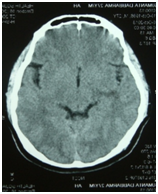

Figure 6 Brain imaging-normal, no basal ganglia calcification.